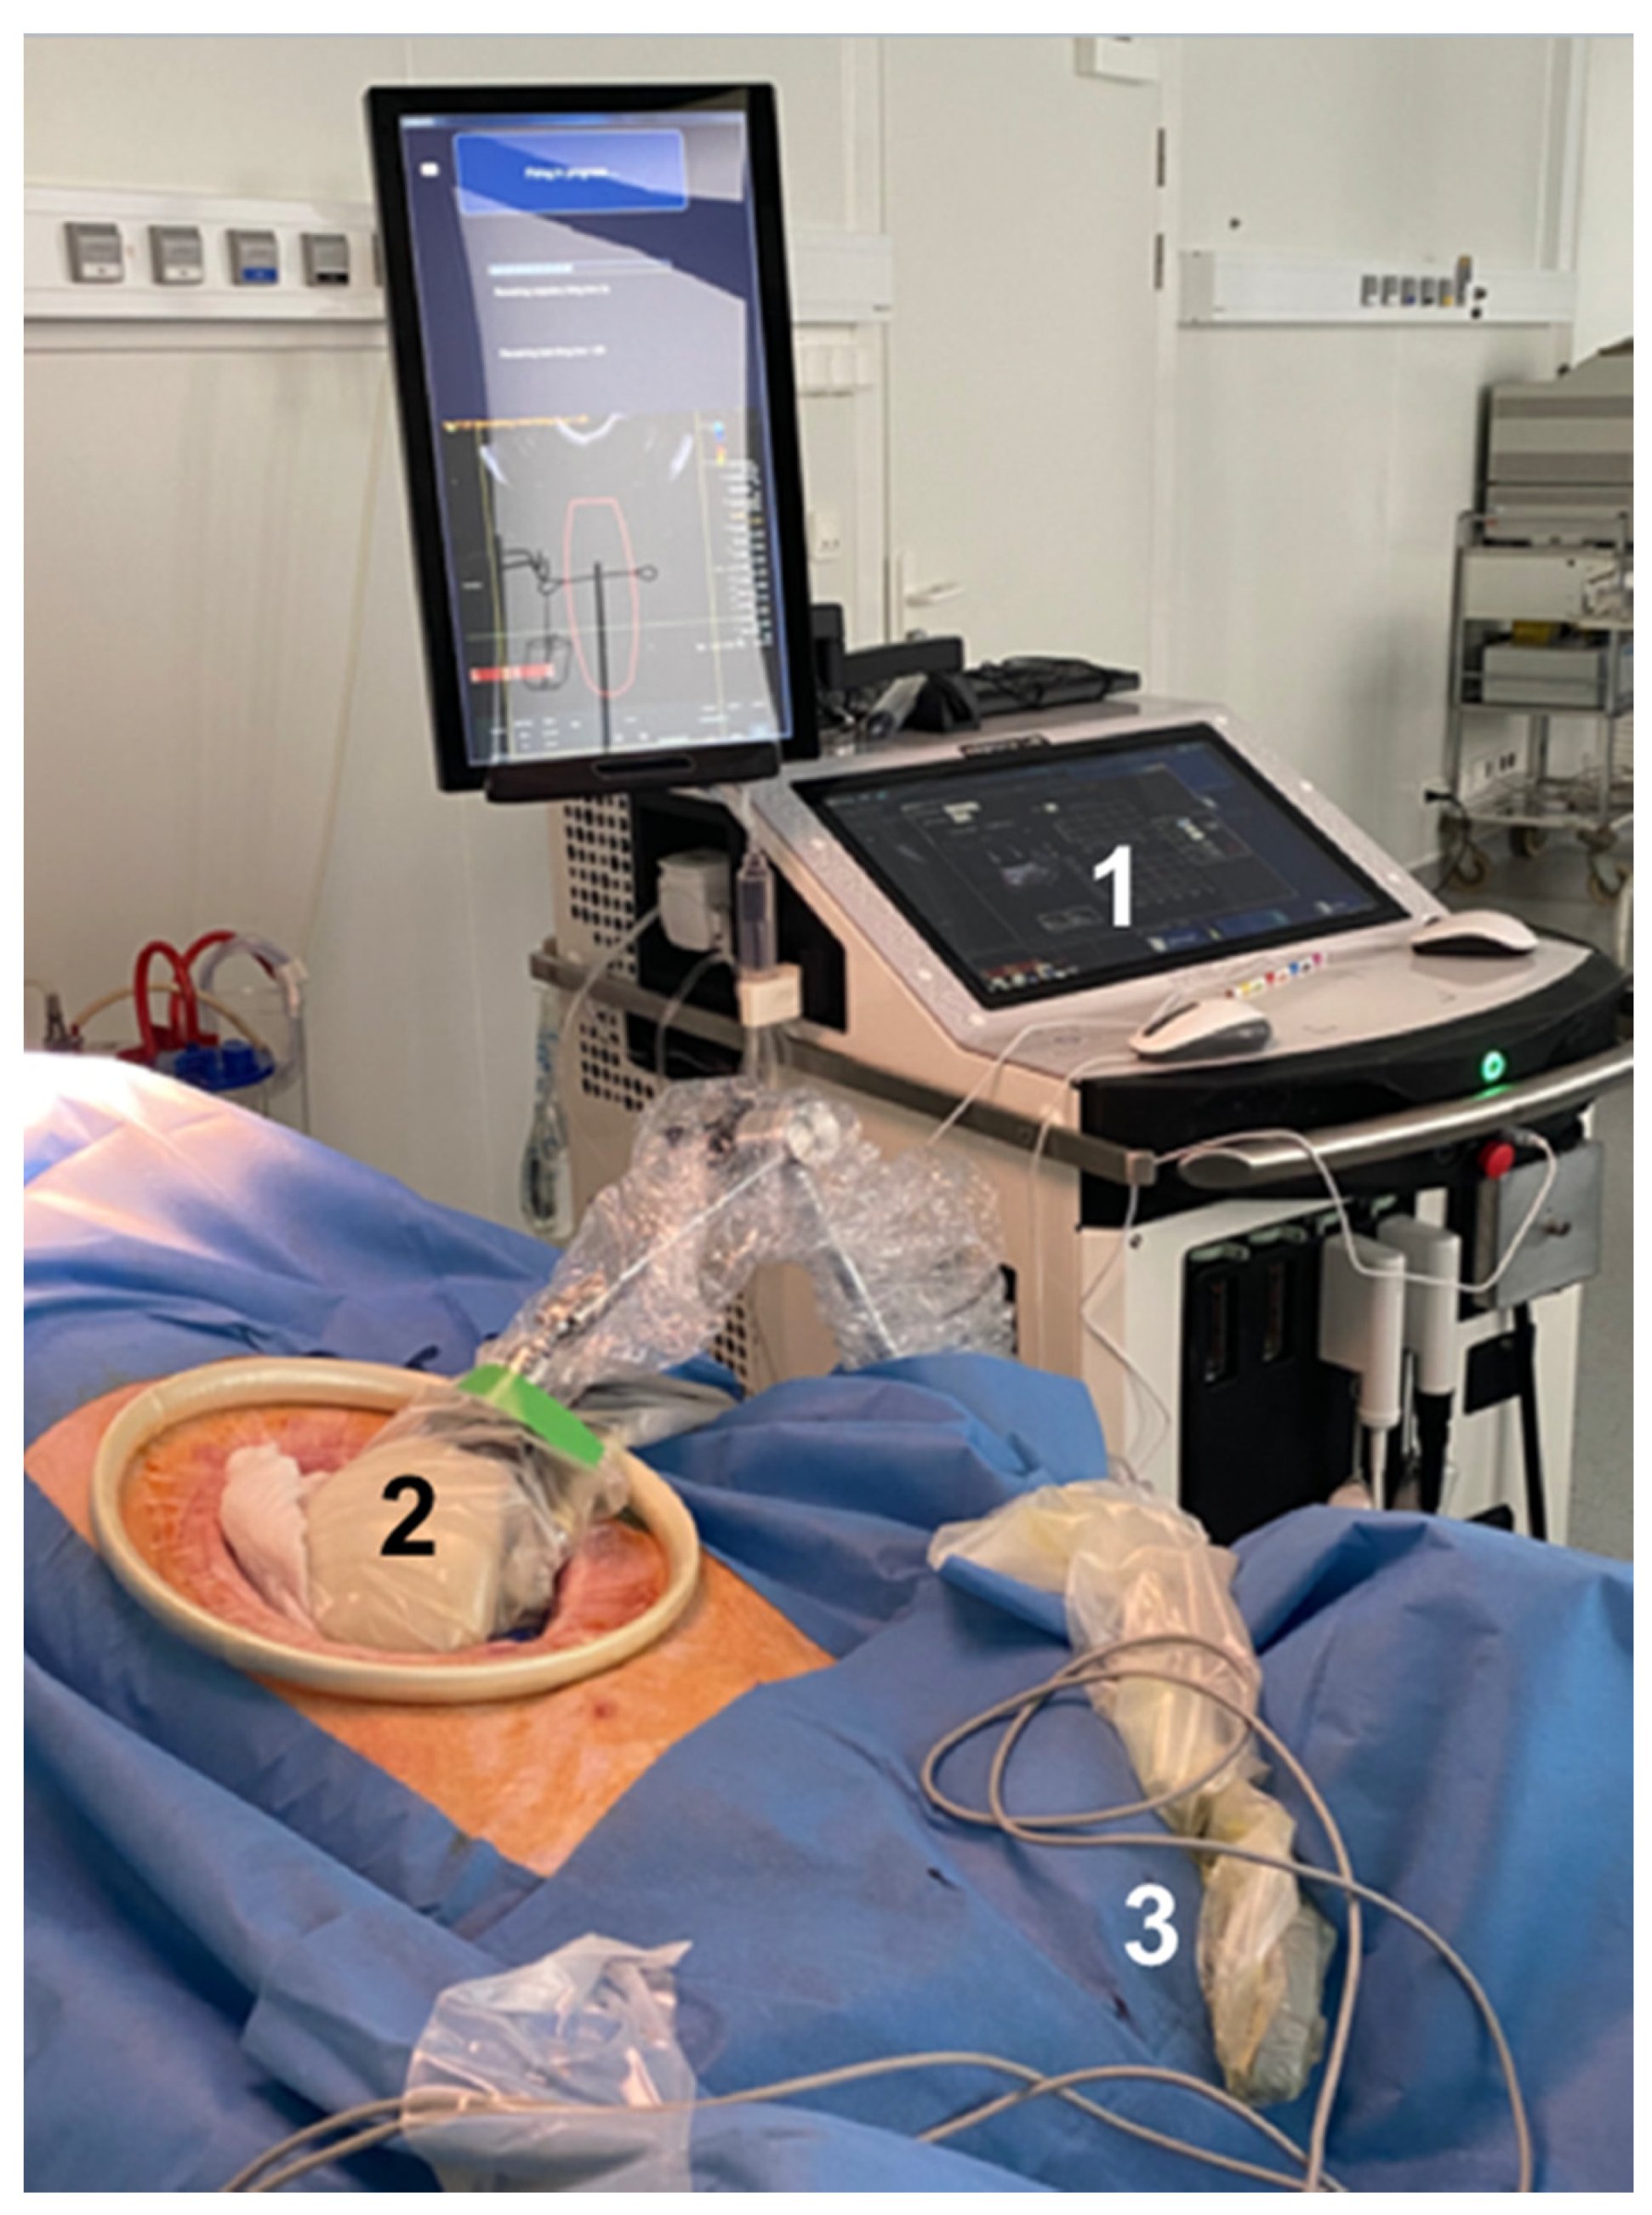

2.2. HIFU Equipment

2.3. Treatment Procedure